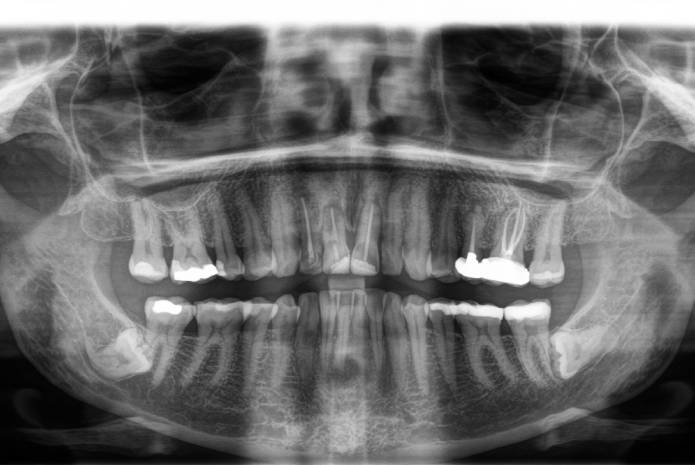

Presentamos el caso clínico de una paciente de 51 años sin antecedentes médicos de interés que acudió por movilidad en los dientes 12, 11 y 21 deseando mejorar su estética dental. La necesidad de extraer más de un diente en el sector estético confirió a este caso un nivel alto de complejidad. Tras 7 años de seguimiento comprobamos un alto índice de estabilidad en el tratamiento realizado.